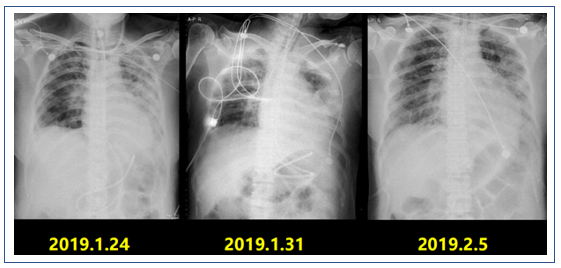

后续患者X线胸片检查结果(图12)。

图4 患者治疗前后X线胸片对比

左:2018年12月31日胸片;右:2019年1月7日胸片

复查X线胸片:双肺多发渗出进展,左肺大片实变(图6)。